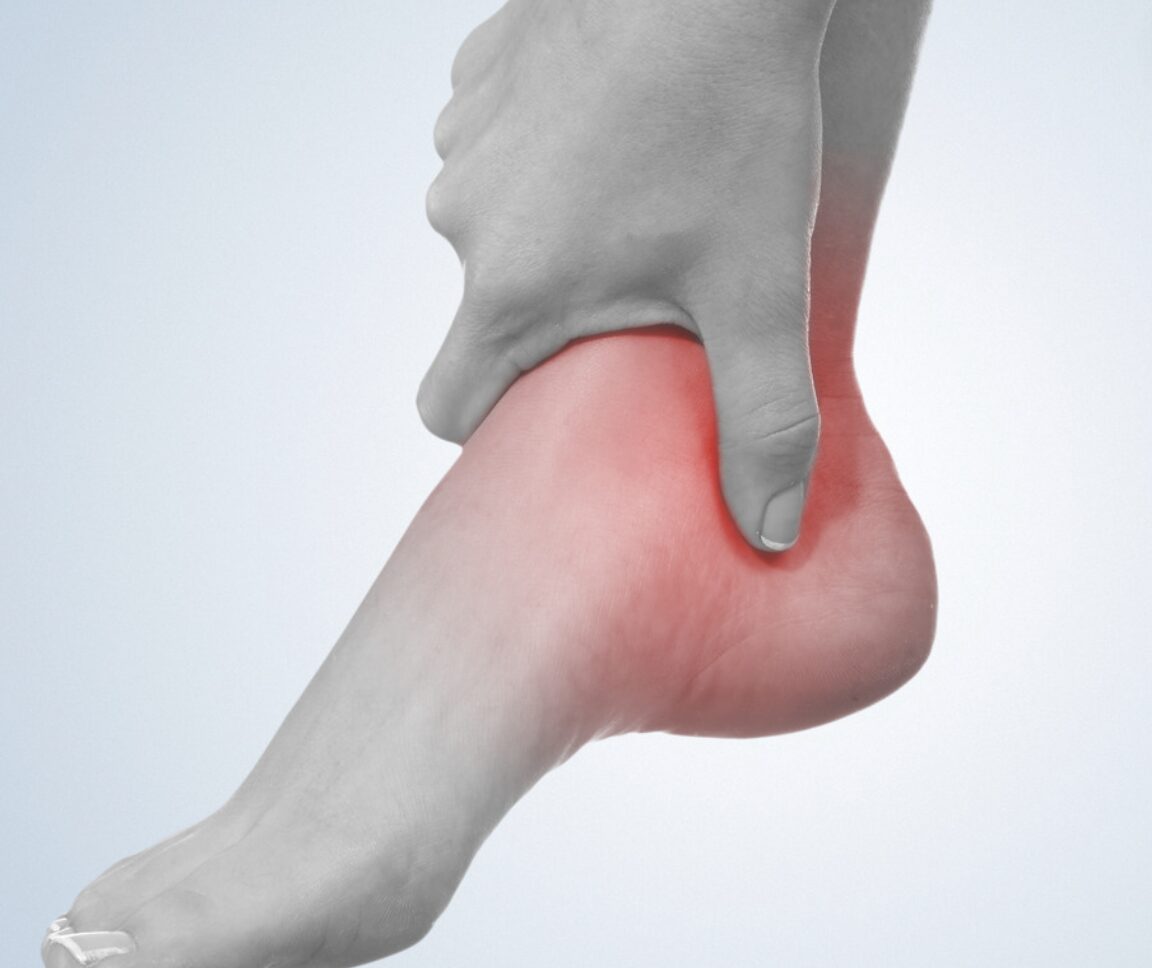

アキレス腱炎・アキレス腱断裂でお困りの方

アキレス腱の痛みや違和感は、日常生活やスポーツに大きな支障を与えることがあります。

ふくらはぎやかかとに痛みがある

歩行やジャンプで負担を感じる

急な痛みで力が入らない

こうした症状がある方は、早めの施術とケアが回復の鍵です。

- ふくらはぎやかかとの上部に痛みや熱感を感じる

- 歩く・走る・階段昇降で痛みが強くなる

- 腫れや腱の硬さ・張りを感じる

- 突然の衝撃音とともにかかとに力が入らない(断裂の可能性)

- 足首を動かすと痛みや違和感が出る